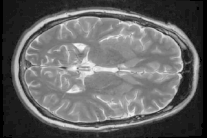

لكنّ فريقاً دولياً من الباحثين تمكن من رسم خريطة لشبكة الروابط بين الخلايا العصبية باستخدام ماسح قوي في تقنية التصوير بالرنين المغناطيسي.

واستخدم الباحثون عمليات مسح بتقنية التصوير بالرنين المغناطيسي لبناء خريطة روابط التشابك بين الخلايا العصبية لأدمغة المتطوعين ومقارنة اوجه الشبه والاختلاف من حين الكثافة والأبعاد.